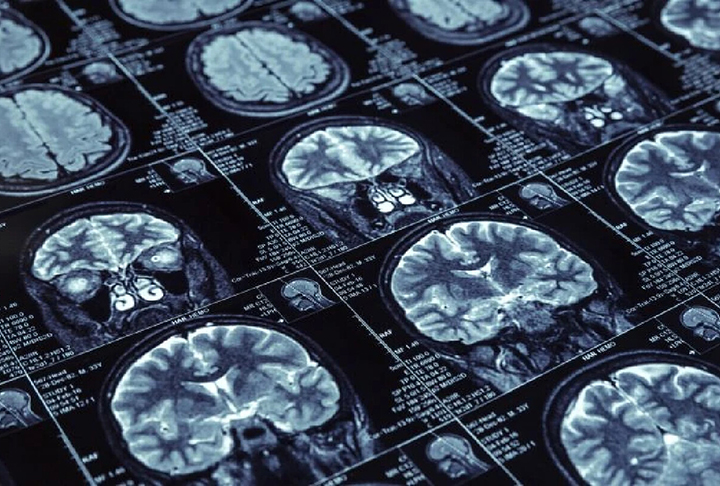

Primeira paciente com Mal de Alzheimer entrou para a história